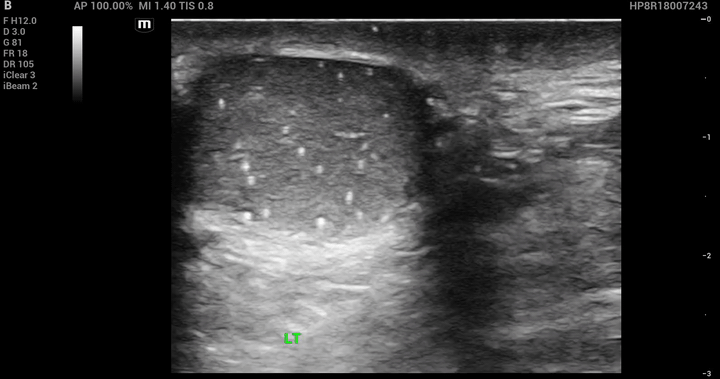

POCUS images of the left testicle:

Findings of bedside ultrasound:

• Multiple punctate, non-shadowing, uniformly sized, hyperechoic foci measuring 1–2 mm within the left testis.

• No testicular mass noted. No anechoic fluid collection around the left testis concerning for hydrocele. No other significant findings.

Diagnosis/Finding: Left testicular microlithiasis.